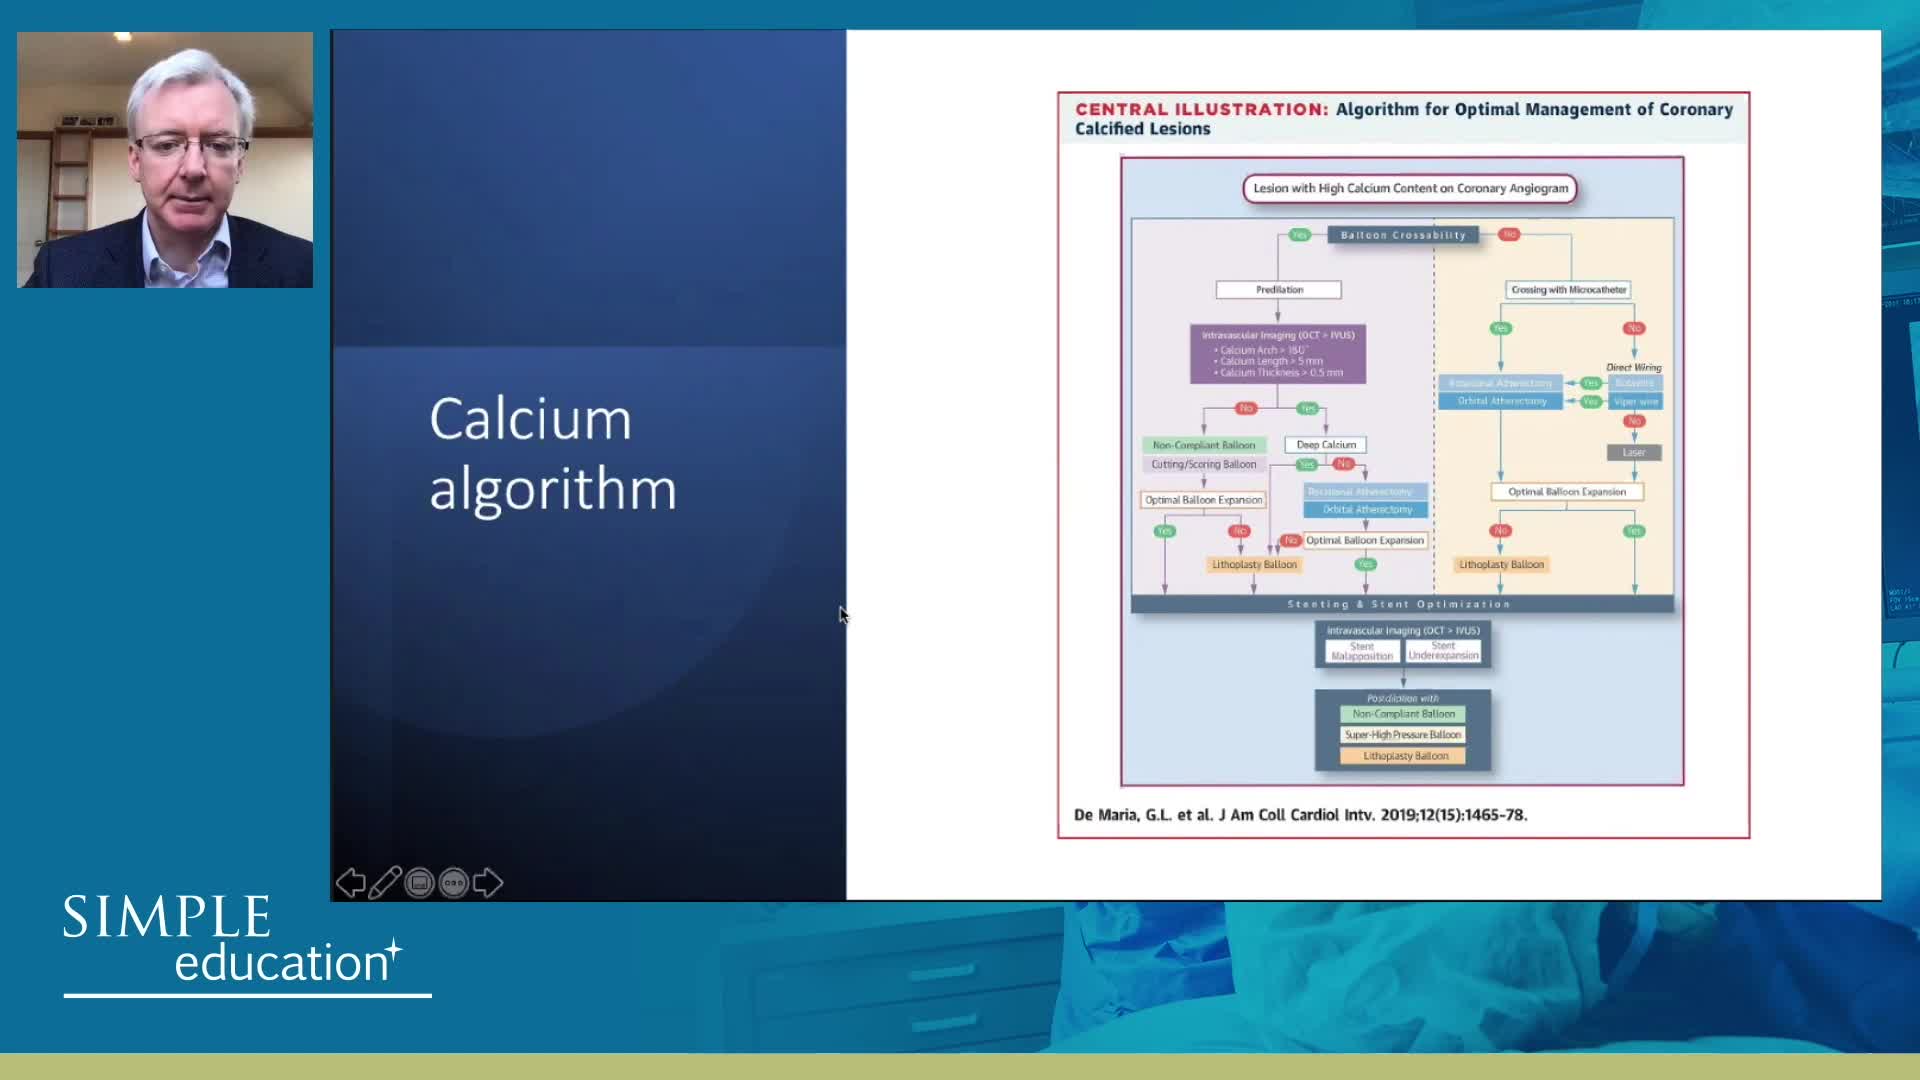

Advanced PCI Course Content

Best practices and personalised medicine in complex PCI - Prof Javier Escaned